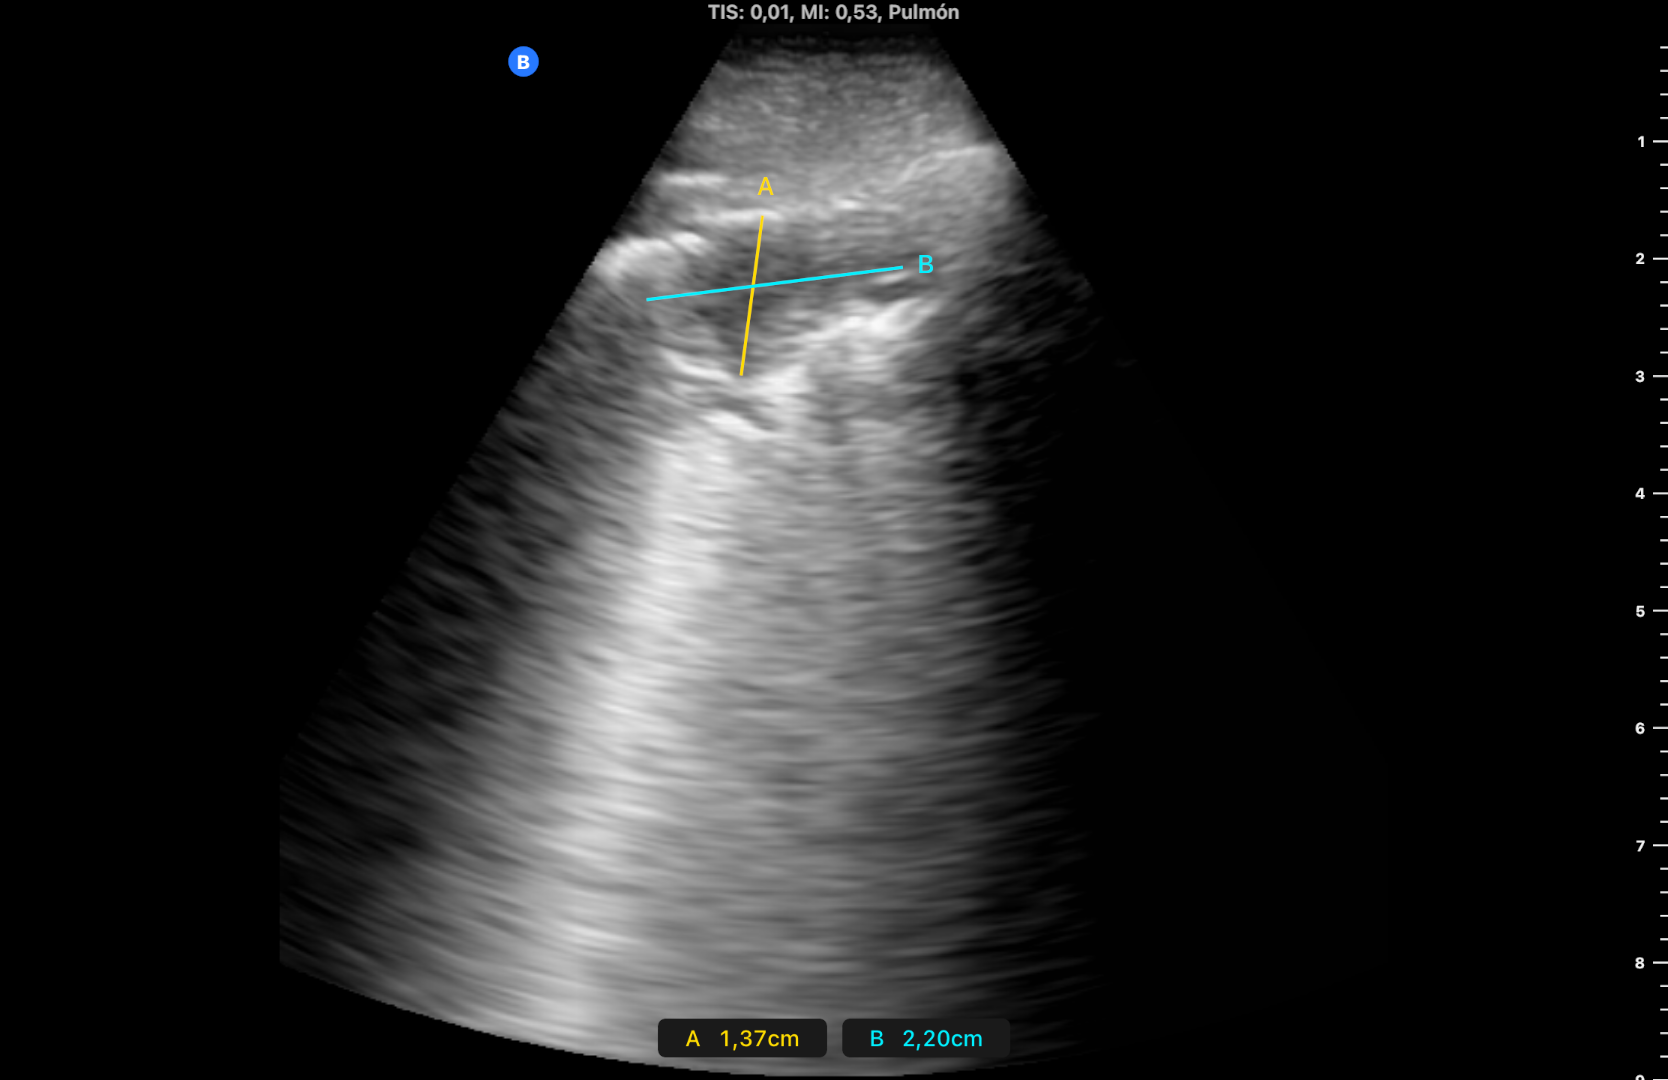

Varón de 95 años exfumador e hipertrofia benigna de próstata, en tratamiento con tamsulosina. Buena capacidad cognitiva con limitación de movilidad por edad y ausencia de ascensor. Aviso a domicilio por catarro de vías altas de 3 días, febrícula de 37,5 ºC desde el día anterior y dolor costal derecho con la tos y movimientos respiratorios. Tiene buen estado general, saturación 95% y en auscultación hipoventila en campo inferior derecho. Se realiza en domicilio ecografía pulmonar con ecógrafo portátil (imagen 1).

Hallazgos ecográficos

Consolidación con broncograma aéreo de 4 x 2 cm en campo posterolateral inferior derecho con leve derrame pleural adyacente al diafragma, y líneas B alrededor de la consolidación (imagen 2).